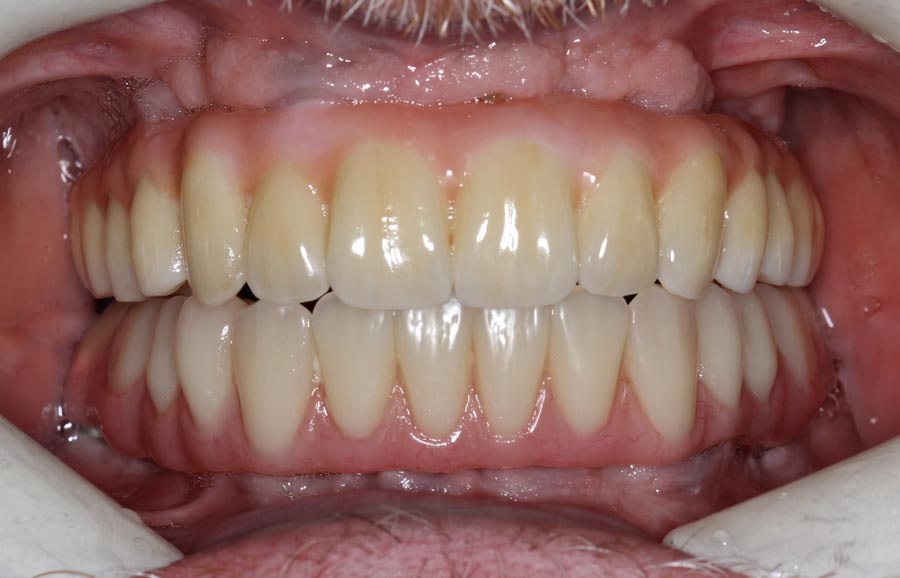

Frontal view of upper implant bridge (intra-oral). Just because the patient is delaying treatment on the lower doesn’t mean we can’t improve it for the year he is waiting. See next picture.

Smile of upper permanent and lower bonded teeth. The patient is starting to learn how to smile, again!